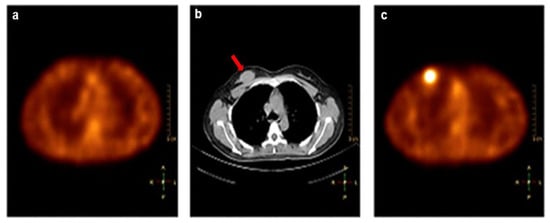

[99mTc]Tc-RGD-BBN, which targets both integrin αvβ3 and GRPR, was developed to improve tumor detection over mono-targeted imaging agents. This study explored the safety, pharmacokinetics, and biodistribution of [99mTc]Tc-RGD-BBN in six healthy volunteers. Additionally, the diagnostic performance of [99mTc]Tc-RGD-BBN was compared with that of [99mTc]Tc-3P4-RGD2 in 6 female patients with metastatic breast cancer []. [99mTc]Tc-RGD-BBN demonstrated clear uptake in 6 palpable lesions, and [99mTc]Tc-3P4-RGD2 demonstrated clear uptake in 5 out of 6 lesions. By IHC analysis, expression of both αvβ3 and GRPR were found in 4 out of 6 cases. One case was only positive for GRPR, and another was only positive for αvβ3. [99mTc]Tc-RGD-BBN would be useful in detecting malignant tumors that are negative for integrin αvβ3 but positive for GRPR expression, as these phenotypes would not be detected by [99mTc]Tc-3P4-RGD2 (Figure 4). Due to the promising imaging results and lower effective radiation dose, [99mTc]Tc-3P4-RGD2 may have the possibility of extending imaging applications to breast cancer screening.

Figure 4.

SPECT/CT images of a breast tumor that is positive for GRPR but negative for integrin αvβ3 expression. (a) [99mTc]Tc-3P4-RGD2 SPECT had no tracer uptake in the lesion. (b) CT scan showed a mass in the right breast (arrow). (c) [99mTc]Tc-RGD-BBN SPECT demonstrated high uptake in the lesion. (Reprinted from Ref. []).